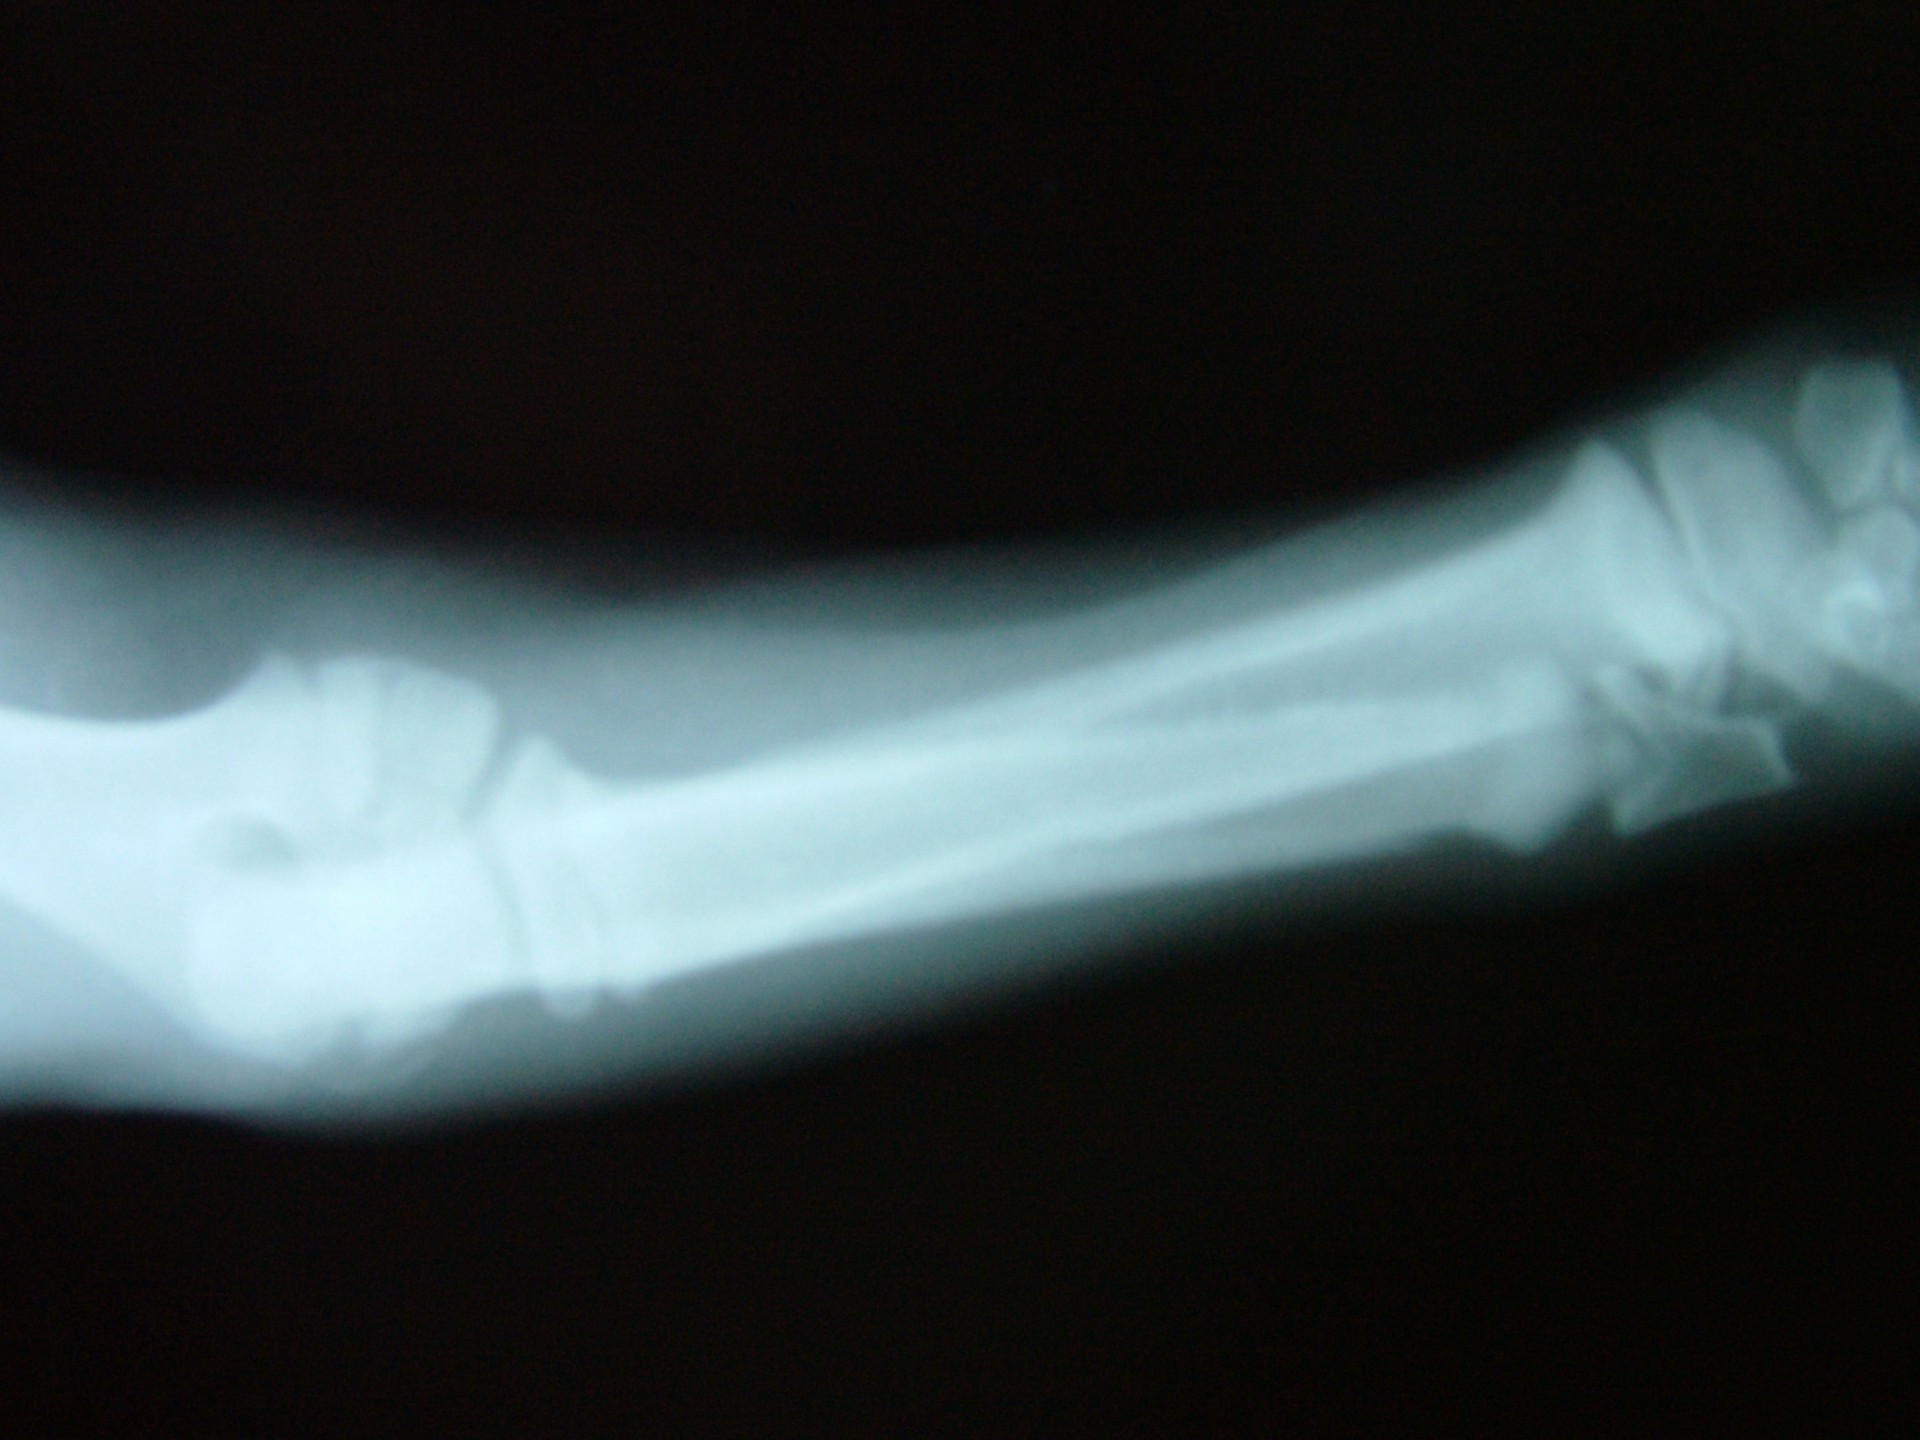

A betegségre jellemző, hogy az ébren klinikai tüneteket mutató állatok altatásban történő vizsgálata (az izmok ellazulása miatt)valamint az érintett végtagról készült röntgen vizsgálat mindig negatív eredménnyel zárul, a csontozatban rendellenesség nem mutatható ki.

A diagnózis felállítása során a legfontosabb, hogy kizárjuk a szintén fiatal állatokra jellemző, a csövescsontok növekedési zónájának lezáródásából adódó végtagdeformitást.